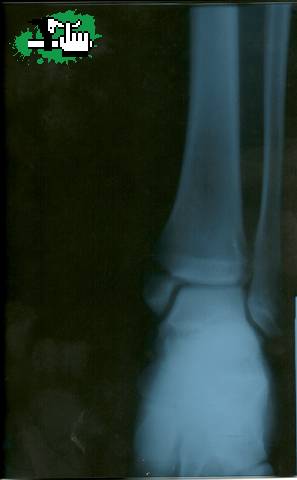

volviendo de apoco hace 10 dias que em sacaron el yeso de la muñeca por una fractura de escafoide (1 clavo) y tibia 2(clavos) hace 5 meces que no tocaba una bici